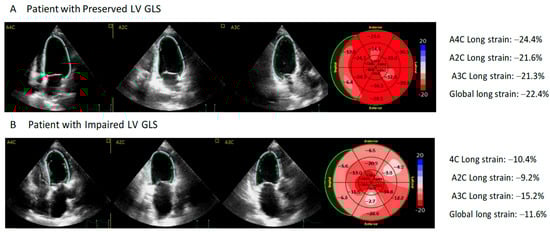

All patients had a normal left ventricular ejection fraction. However, after assessing GLS, we observed that this parameter was reduced in 11 of the 31 patients (35.5%) (Figure 2). Comorbidities such as hypertension and chronic kidney disease were more common in patients with left ventricular dysfunction determined by GLS. These patients also had higher plasma hs-cTnI levels (23.7 vs. 3.2 ng/L; p < 0.05) and NT-proBNP levels (753 vs. 81 pg/mL; p < 0. 05). Moreover, 45.5% of patients with reduced GSL had elevated troponin I plasma levels. No differences were observed for plasma markers of inflammation (interleukin 6 and C-reactive protein) (Table 1 and Table 2).

Panel A shows an example of a 65-year-old patient with normal left ventricular global longitudinal strain (LV GLS) and 1.5 ng/L of high-sensitivity troponin I (hs-TnI); a longitudinal strain of −22.4% was obtained from the bull’s eye plot derived from two-dimensional speckle tracking imaging. Panel B shows results from a 72-year-old patient with impaired LV GLS and 121.4 ng/L of hs-TnI; a longitudinal strain of −11.6% was obtained from the bull’s eye plot derived from two-dimensional speckle tracking imaging.